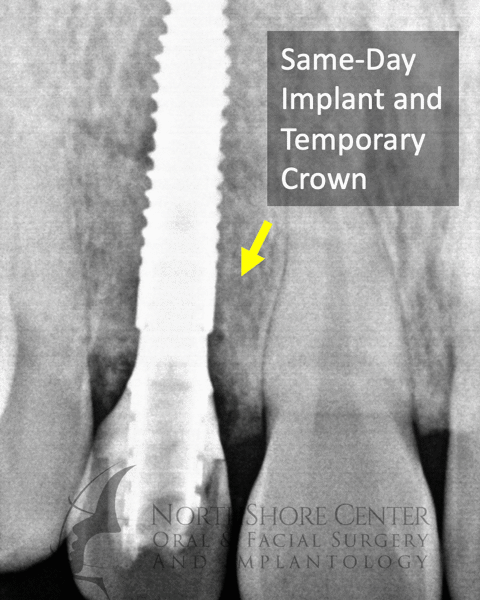

The NSCOFS Difference: Single Surgery implant placement

Losing a front tooth can be particularly stressful and traumatic for patients. Oftentimes when a front tooth needs to be removed you have to wear a removable device (a “flipper” or “essix retainer”) to hide the missing tooth. At NSCOFS we have refined the technique of immediate implant placement with a temporary crown so oftentimes you never have to go without your tooth and don’t have to wear a bulky removable device.

For patients with a big smile, immediate temporary crowns also preserve your natural soft tissue, preventing the appearance of gum recession and tissue defects.

case 1: Fractured Tooth #7 on an 18-year old Male